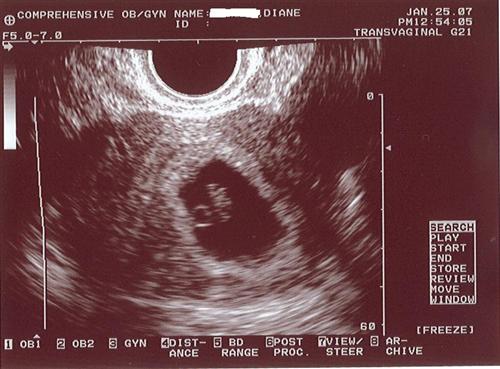

Meet Our Bean!!! (with Pics)

Went for the 1st sono today! I cant even put into words how it felt to see that little heart beating so fast. She said the baby is the right size and the estimated due date is accurate. The bean is about 1/2" long.